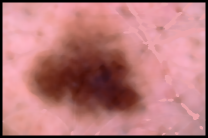

Automated segmentation of a skin lesion is a complex issue, as the possible casuistry that can appear in the images is very diverse. The main problems that can de found in the image which make segmentation difficult are as follows:

1. Presence of hair; 2. Other artifacts such as electronic letters, rulers, ink and color charts, etc.; 3. Dark rectangular or circular marks around it (a consequence of shadow); 4. Flashes; 5. Lighting problems: apart from the problem with dark marks and flashes that have already been mentioned, in some cases one part of the image turns out to be darker than another (a common cases is that the part of the skin beside the circular marks is often darker as it is less brightly lit, and some images also turn out to be darker than others; 6. As a result of the oil used to acquire many images, there may be distortion problems and bubbles; 7. Presence of blood vessels; 8. Presence of regression areas and blue-whitish veil –in many cases these structures have greater intensity than the skin surrounding the lesion; 9. Hypopigmentation areas which are confused with skin; 10. Many colors in the image; 11. Different lesions within the same image; 12. Presence of inflamed area around the lesion; 13. Low contrast of the lesion in relation to the skin; 14. Hardly any skin is visible on occasions, and there is even no skin at all in some images; 15. What in some images has skin color and texture, in others is part of the lesion; 16. Skin color and texture is different among individuals.